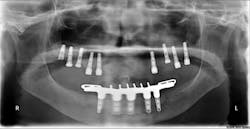

Prior to implantation, an investigation of the planned implant site is required to visualize the available bone and surrounding anatomical structures and augmented areas that could be affected. For this process, CBCT data is critically important in planning for the insertion of not only single implants, but also in the surgical treatment planning for multiple implants (Dreiseidler et al.).

A CBCT scan provides precise information about pathology, the locations and dimensions of vital anatomical structures, bone quality, and any issues that might interfere with treatment planning. The Kodak 9000 3-D extraoral imaging system allows for a broad overview of the patient's dentition with one of the most accurate panoramic images available.

It also allows for the 3-D evaluation of an arch, either in sections or an extended field of view (FOV) option, allowing the full arch to be viewed as a whole three dimensionally. This view helps practitioners correctly identify the region of interest the first time, which results in lower cost to patients because less time and money is consumed for repeated office visits. (See Fig. 3)

When detecting pathology, 3-D imaging makes it easier to develop a treatment plan. The Kodak 9500 cone beam 3-D system provides a larger FOV, which allows for treatment planning of complex implant cases involving both arches. A large FOV also provides incidental findings that may prove valuable in a patient's overall assessment. While locating vital anatomical structures - for example, the maxillary sinus, temporomandibular joints, and the mandibular nerve canal - any abnormalities found can impact implant planning (Hatcher). Common incidental findings include plaque, carotid arteries, sinus pathology, craniofacial lesions, and more.